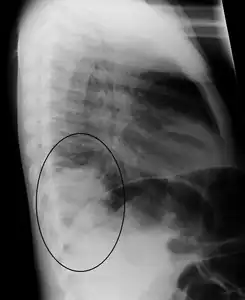

- Right upper lobe pneumonia as marked by the circle.

- Right lower lobe pneumonia as seen on a lateral CXR